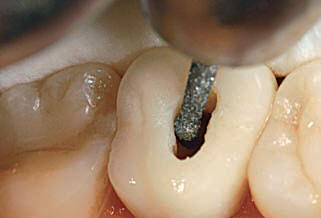

Usted debe rectificar las paredes y no el "Piso" de dicha cámara. Para este fin el mercado ofrece las fresas de Batt o en la actualidad la fresa Endo Z, que presentan la punta inactiva, para no producir una perforación.

Algunos autores consideran  a la conformación de la entrada de los conductos, como parte de la rectificación de la cámara pulpar. Ver imagen derecha Superior.

• E: Conformación del acceso a los conductos en el tercio coronal con fresas de Gates Glidden.

El resultado final debe ser una cavidad de acceso que permita a los instrumentos endodóncicos alcanzar los orificios de entrada de los conductos sin interferencia alguna y lo más rectilíneamente posible. Ver imágenes derecha.